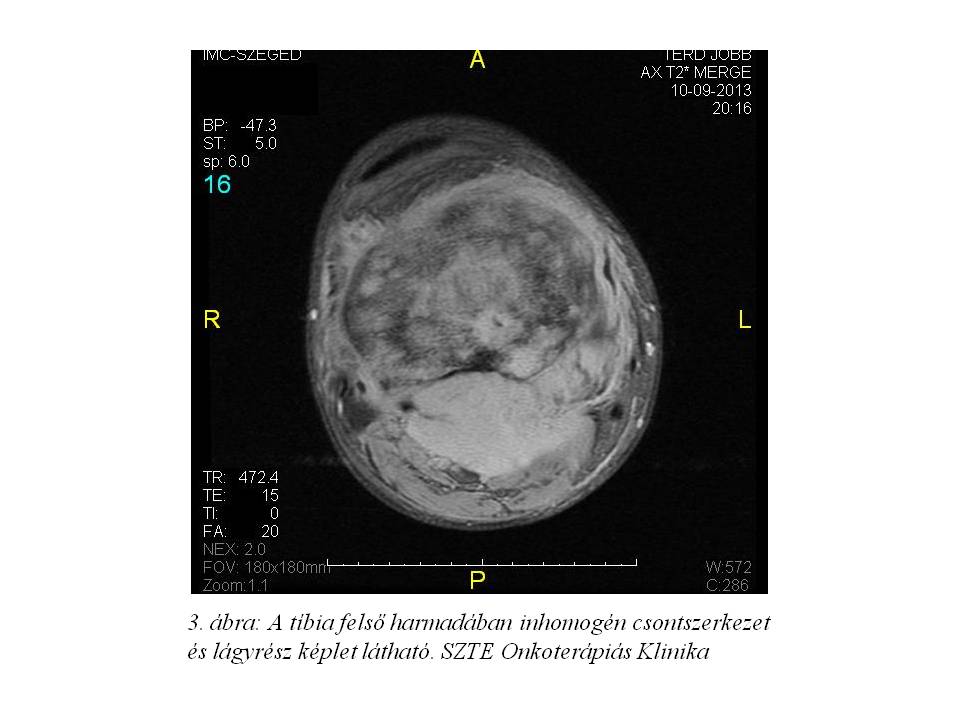

dolt. Júliusra a fájdalom fokozatosan erősödött, RTG vizsgálat (1. ábra) készült, mely traumás eltérést nem írt le, lokális Diprophos-Diclac terápia indult. Fájdalma nem mérséklődött, ellenben folyamatos dagadás és térdhajlati terime növekedést észlelt, MRI (2. ábra, 3. ábra) készült, mely alapján sürgős biopsia történt. A tibia biopsia szövettana desmoplastikus kis kereksejtes tumort (DSRCT) véleményezett, habár a tumor lokalizációja extrém ritka. A DSRCT agresszív, malignus tumor, kifejezetten rossz prognózissal (median túlélés: 17-25 hónap). Általában a primer tumor a hasüregben alakul ki, peritonealis terjedés az elsődleges, majd limfatikus és hematogén áttétképződés, különösen a májba. Staging vizsgálatai során disszeminált csontérintettséget, limfatikus és pulmonalis metasztázisokat írtak le (4. ábra, 5. ábra). A szakirodalom áttekintését követően 2013.10.14-én VIDE (Vincristine, Ifosfamide, Doxorubicin, Etoposide) kemoterápiás, ill. a disszeminált csontérintettség miatt zoledronsav kezelést kezdtünk. A felvételkor csak segédeszközzel, és igen nehezen mozgott, idejének több mint 50%-át ágyban töltötte, állandó medencefenék, keresztcsonti zsibbadásról, vizelet- és széklet-ürítési panaszokat említett.